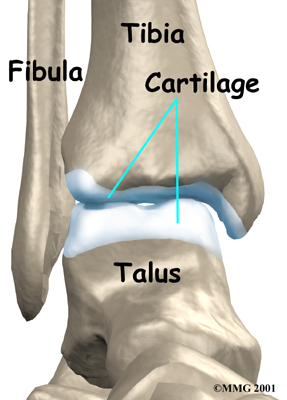

The ankle joint is made up of three bones: the lower end of the tibia (shinbone), the fibula (the small bone of the lower leg), and the talus (the bone that fits into the socket formed by the tibia and fibula). The talus sits on top of the calcaneus (the heelbone).

Inside the joint, the bones are covered with a slick material called articular cartilage. Articular cartilage is the material that allows the bones to move smoothly against one another in the joints of the body.

The cartilage lining is about one-quarter of an inch thick in most joints that carry body weight, such as the ankle, hip, or knee. It is soft enough to allow for shock absorption, but tough enough to last a lifetime - as long as it is not injured.